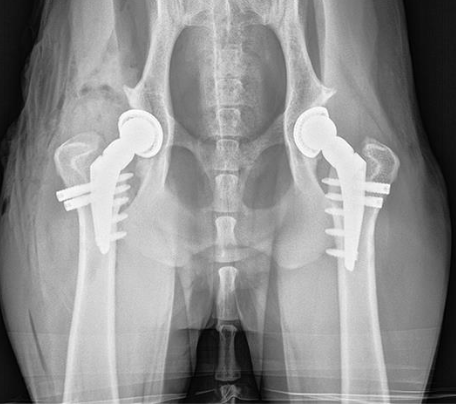

Total hip replacement in Dogs

The other type of hip dysplasia surgery is Total hip replacement (THR). Total hip replacement in dogs involves the removal of the ball and the socket portion of the joint and replacement with a new ball-and-socket, hence “total” hip replacement. Total hip replacement (THR) in dogs is somewhat the opposite of FHO:

- Total hip replacement (THR) in dogs can provide near-normal or normal function. In other words, function and pain relief is superior to what can be achieved with FHO or FHNE

- Canine Total hip replacement (THR) is more expensive than FHO or FHNE.

- Total hip replacement (THR) in dogs has a low complication rate, but some complications can be very problematic and require removal of the implants. Complications of dog total hip replacement can include infection, dislocation, and fracture for example.

- Post-op care for canine Total hip replacement (THR) surgery in dogs requires restriction (ie rest and leashed walking) to try and avoid any of the aforementioned complications

This patient has had bilateral total hip replacements. Each side is a separate surgery, generally staged several months apart.